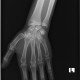

ALO Dokter. Pasien usia 19 tahun keluhan nyeri pergelangan tangan susah di gerakan, tanda inflamasi (+), pemeriksaan tidak terdapat krepitasi, nyeri tekan (+), rom terbatas nyeri, pasien jatuh saat mengejar layangan dengan tangan kiri sebagai topangan. Gambaran radiologi sebagai berikut tidak ada bacaannya, mohon arahan rekan sejawat semua. Terimakasih

ALO Dokter, sepertinya ada garis fraktur pada scaphoid. Untuk lebih jelasnya, bisa dilakukan CT scan.